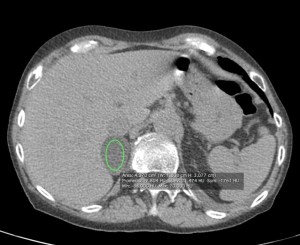

Calculamos la Fórmula WASHOUT, optaremos por la absoluta.

(PORTAL – TARDÍA / PORTAL – Sin CONTRASTE) x 100% = (54,8 – 12,1 / 54,8 – 2,08) x 100 = 80,7 %

El porcentaje de lavado es > 60%. Todos estos hallazgos establecen el diagnóstico de ADENOMA SUPRARRENAL.